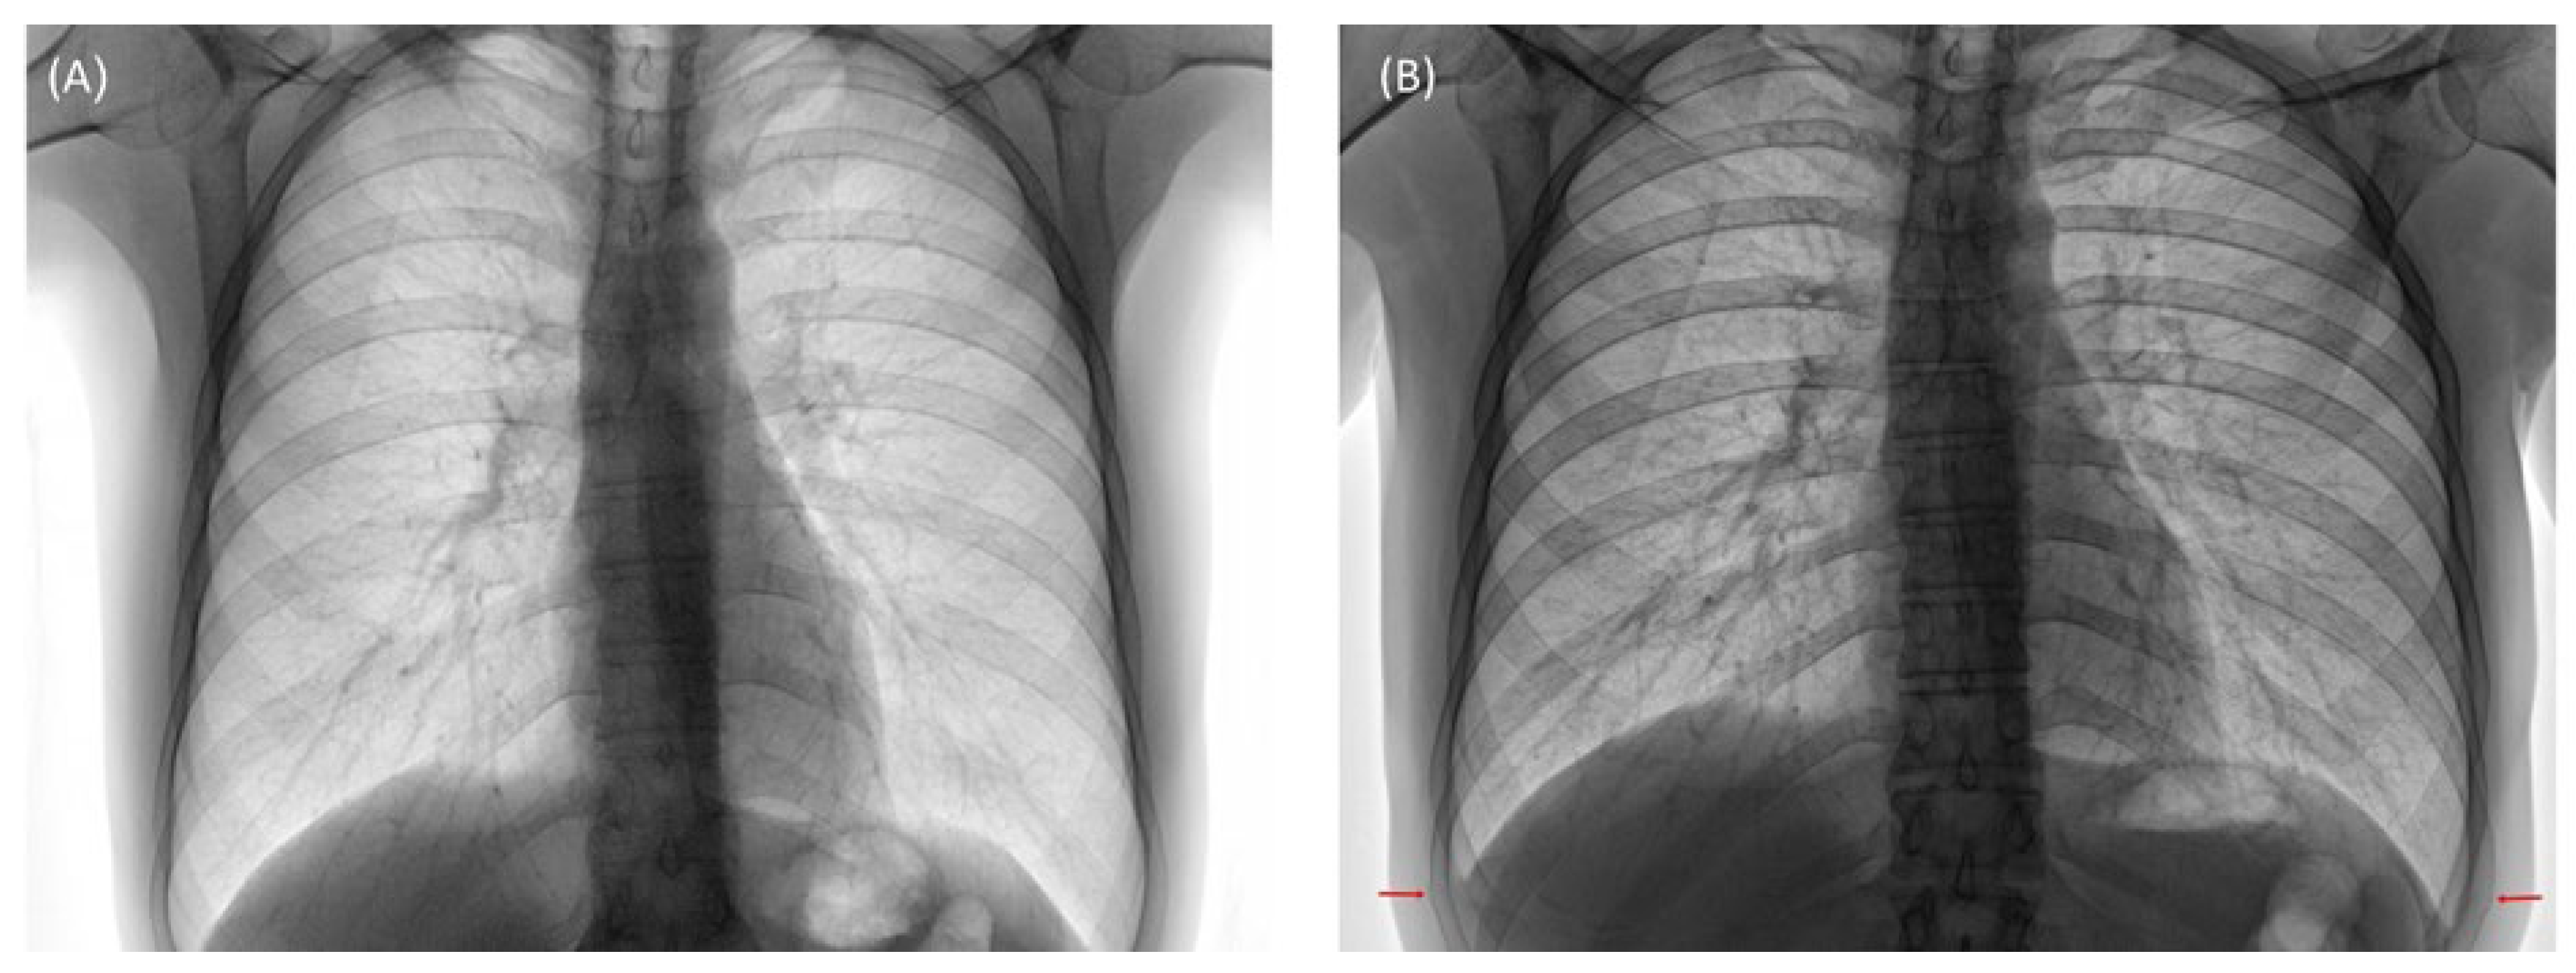

- Daccache, A.; Haddad, J.; Ghanem, A.; Feghali, E.J.; El Osta, B. Cough-Induced Rib Fracture in a Smoker: A Case Report. J. Med. Case Rep. 2020, 14, 147. [Google Scholar] [CrossRef]